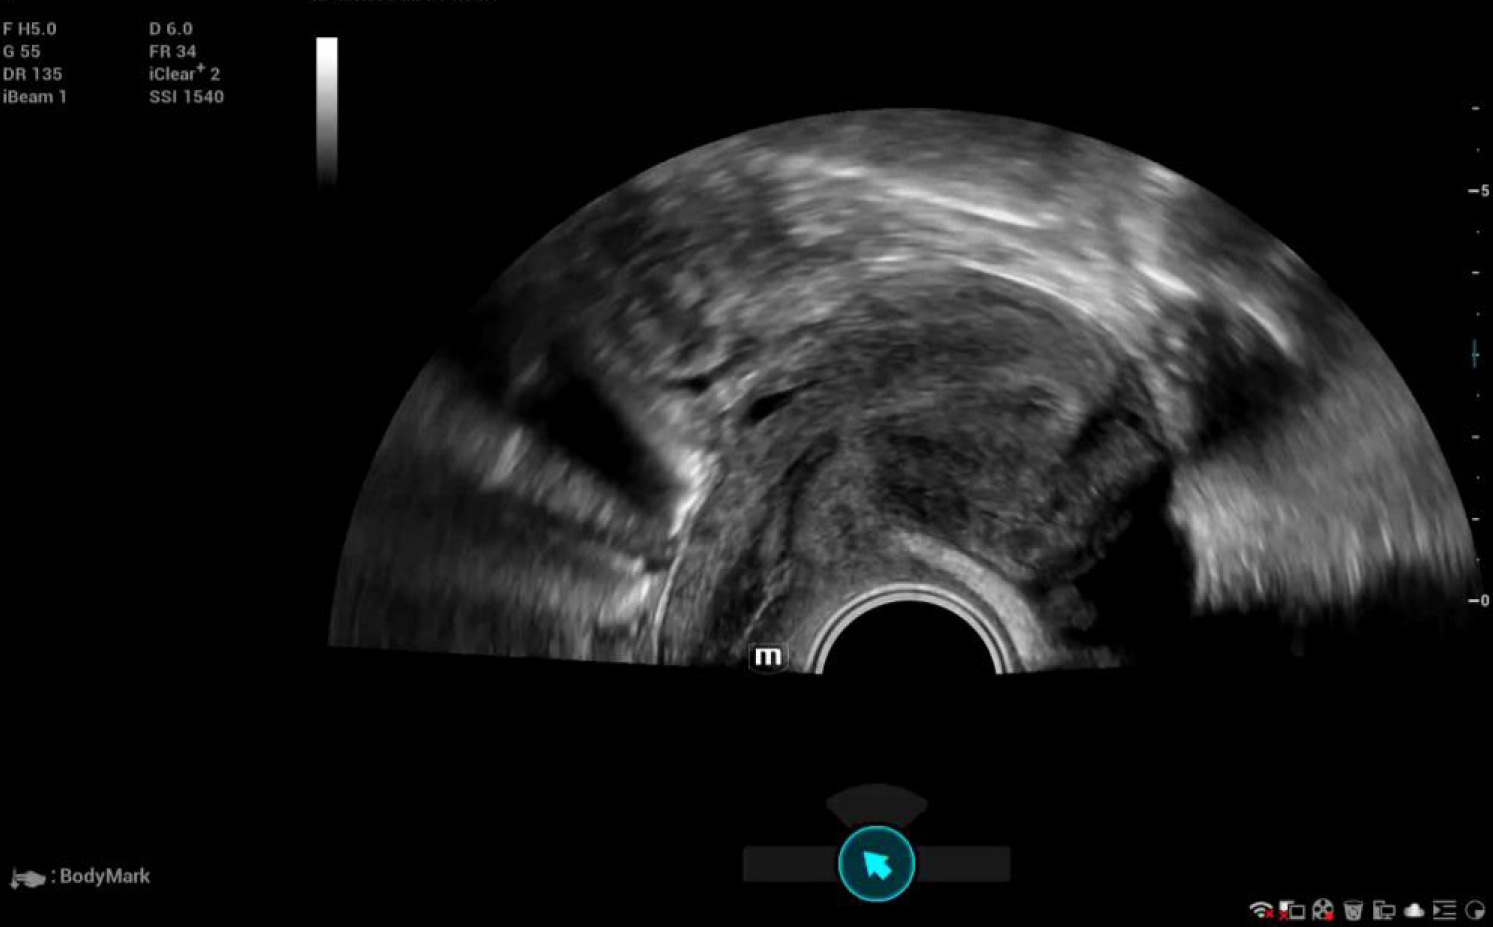

Полноценное интеллектуальное решение для диагностики матки, для легкой и быстрой оценки эндометрия

- Автоматическое распознавание матки

- Автоматическая подстройка зоны интереса и положения до оптимального

- Автоматический объемный рендеринг эндометрия